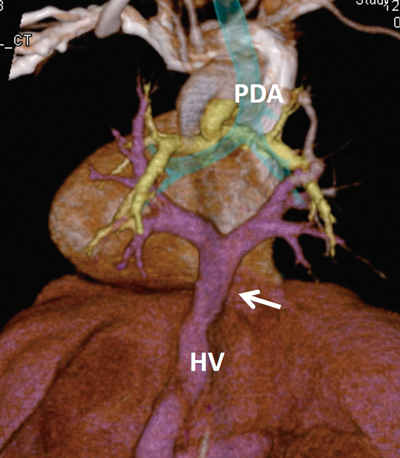

Pediatric Cardiology and Cardiac Surgery 32(3): 215-220 (2016)

Fig. 5 Postoperative multiple-detector computed tomography (A) and angiography (B)

The left pulmonary veins return to the atrium without stenosis.

TCPC(Total cavopulmonary connection)手術(Fig. 6B)と経過

2歳5ヵ月(体重7.8 kg)で手術を行った.胸骨再正中切開人工心肺心拍動下に行った.中心肺動脈は大動脈背側を十分に剥離して,thin wall ePTFE graftをパッチとして拡大した.18 mmφ ePTFEグラフトを心外導管として用いて,TCPC手術を行った.体外循環時間:196分であった.現在4歳8ヵ月,PVOの再発なく(Fig. 5B)外来経過観察中である.